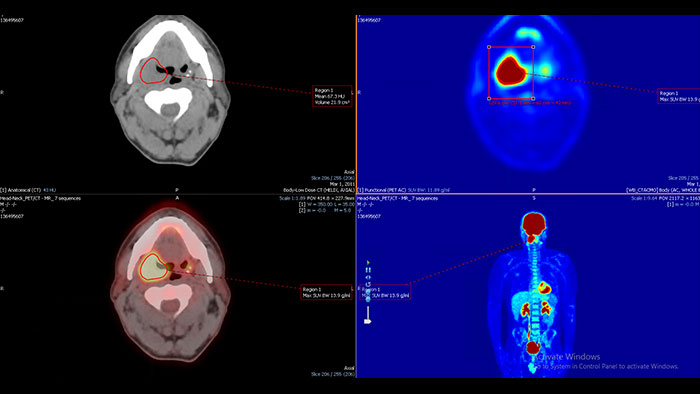

Enhanced user experience for NM reading with a leading NM viewing solution

A comprehensive NM solution, designed to enhance productivity of PET/CT and NM reading. It offers a solution for handling multiple studies requiring rigorous quantification of MV data**.

Benefits

* Mirada is a registered trademark of Mirada inc.

** Please contact local Philips representative for details on multivendor coverage.